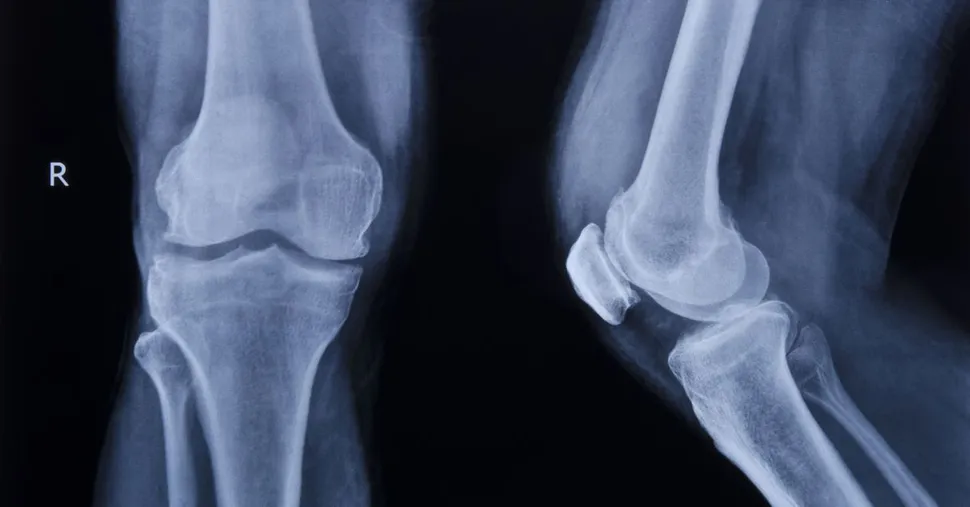

XGEVA is a fully human monoclonal antibody that binds to and neutralizes RANK ligand (RANKL) – a protein essential for the formation, function and survival of osteoclasts, which break down bone – thereby inhibiting osteoclast-mediated bone destruction. XGEVA is currently the number one prescribed bone-targeting agent in the U.S. for the prevention of skeletal-related events in patients with bone metastases from solid tumors. Additional regulatory applications for XGEVA for the prevention of skeletal-related events in patients with multiple myeloma are underway and have been submitted to health authorities worldwide. The drug was compared to Zometa (zoledronic acid) in the '482 study that involved 1,781 patients (859 in each study arm). Patients received either subcutaneous XGEVA 120 mg and IV placebo every four weeks or IV zoledronic acid 4 mg (adjusted for renal function) and subcutaneous placebo every four weeks. XGEVA was found to have the same impact as zoledronic acid. Overall survival was comparable between XGEVA and zoledronic acid. When progression free survival was compared, XGEVA was superior at 46.1 months compared to zoledronic acid's 35.4 months. Osteonecrosis of the jaw is a known side effect of bone strentheners. In the '482 study, ONJ was confirmed in 4.1% of XGEVA patients and 2.8% of zoledronic acid patients. More than 90 percent of patients develop bone (osteolytic) lesions during the course of the disease. Preventing bone complications is a critical aspect of caring for patients with multiple myeloma, because these events can cause significant pain and impact morbidity.